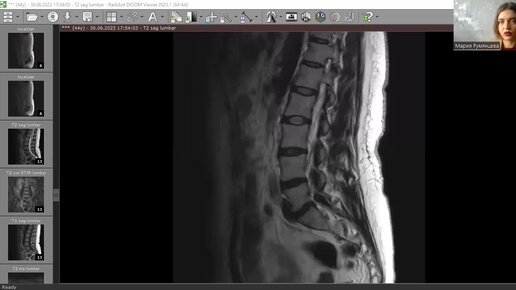

после удаления грыжи диска